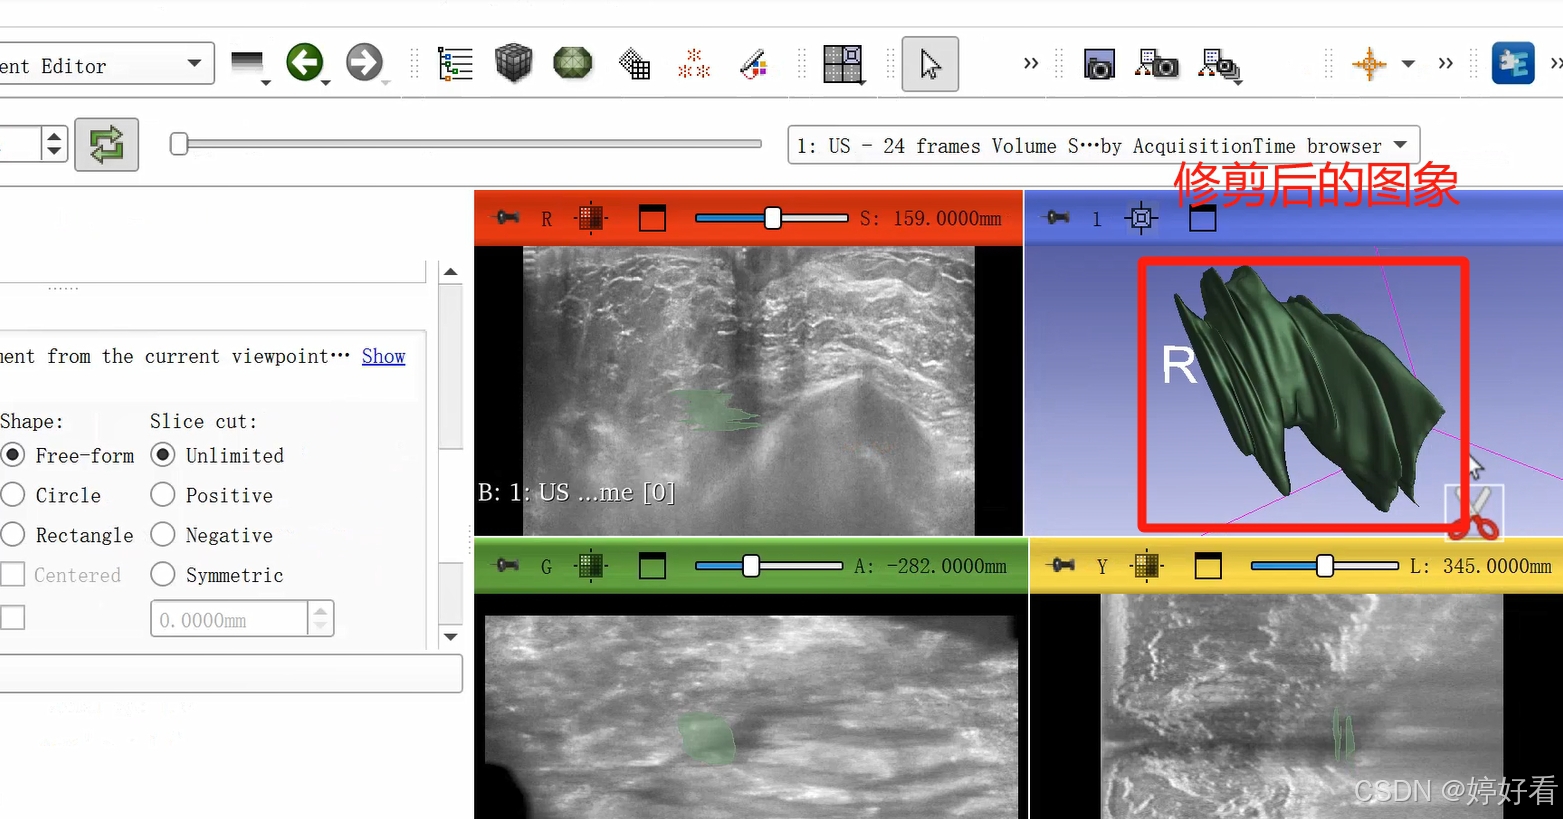

2.8 剪刀功能

剪刀功能的选项较多。以第一个Erase inside功能为例,也就是把圈起来部分里面的内容减掉。